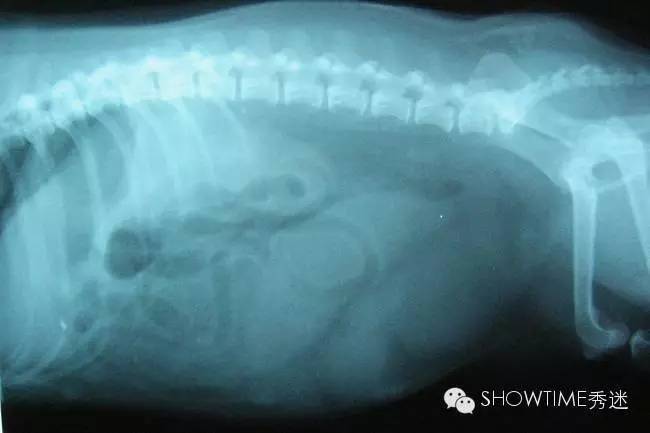

子宫蓄脓一般分为两大类,开放型和封闭型。

封闭型的症状:(注:封闭型因症状相对不明显,不大容易被察觉)

1、从狗狗的外阴部,看不出黄色粘液状的分泌物,因为脓汁的堆积,堵塞阴部的排泄,这种情况会比较严重,可能引发一系列的并发症,如败血症、内毒血症等等;

4、腹部胀大、严重脱水;

5、情况严重时会出现昏迷、休克等症状,甚至可能直接导致狗狗死亡。